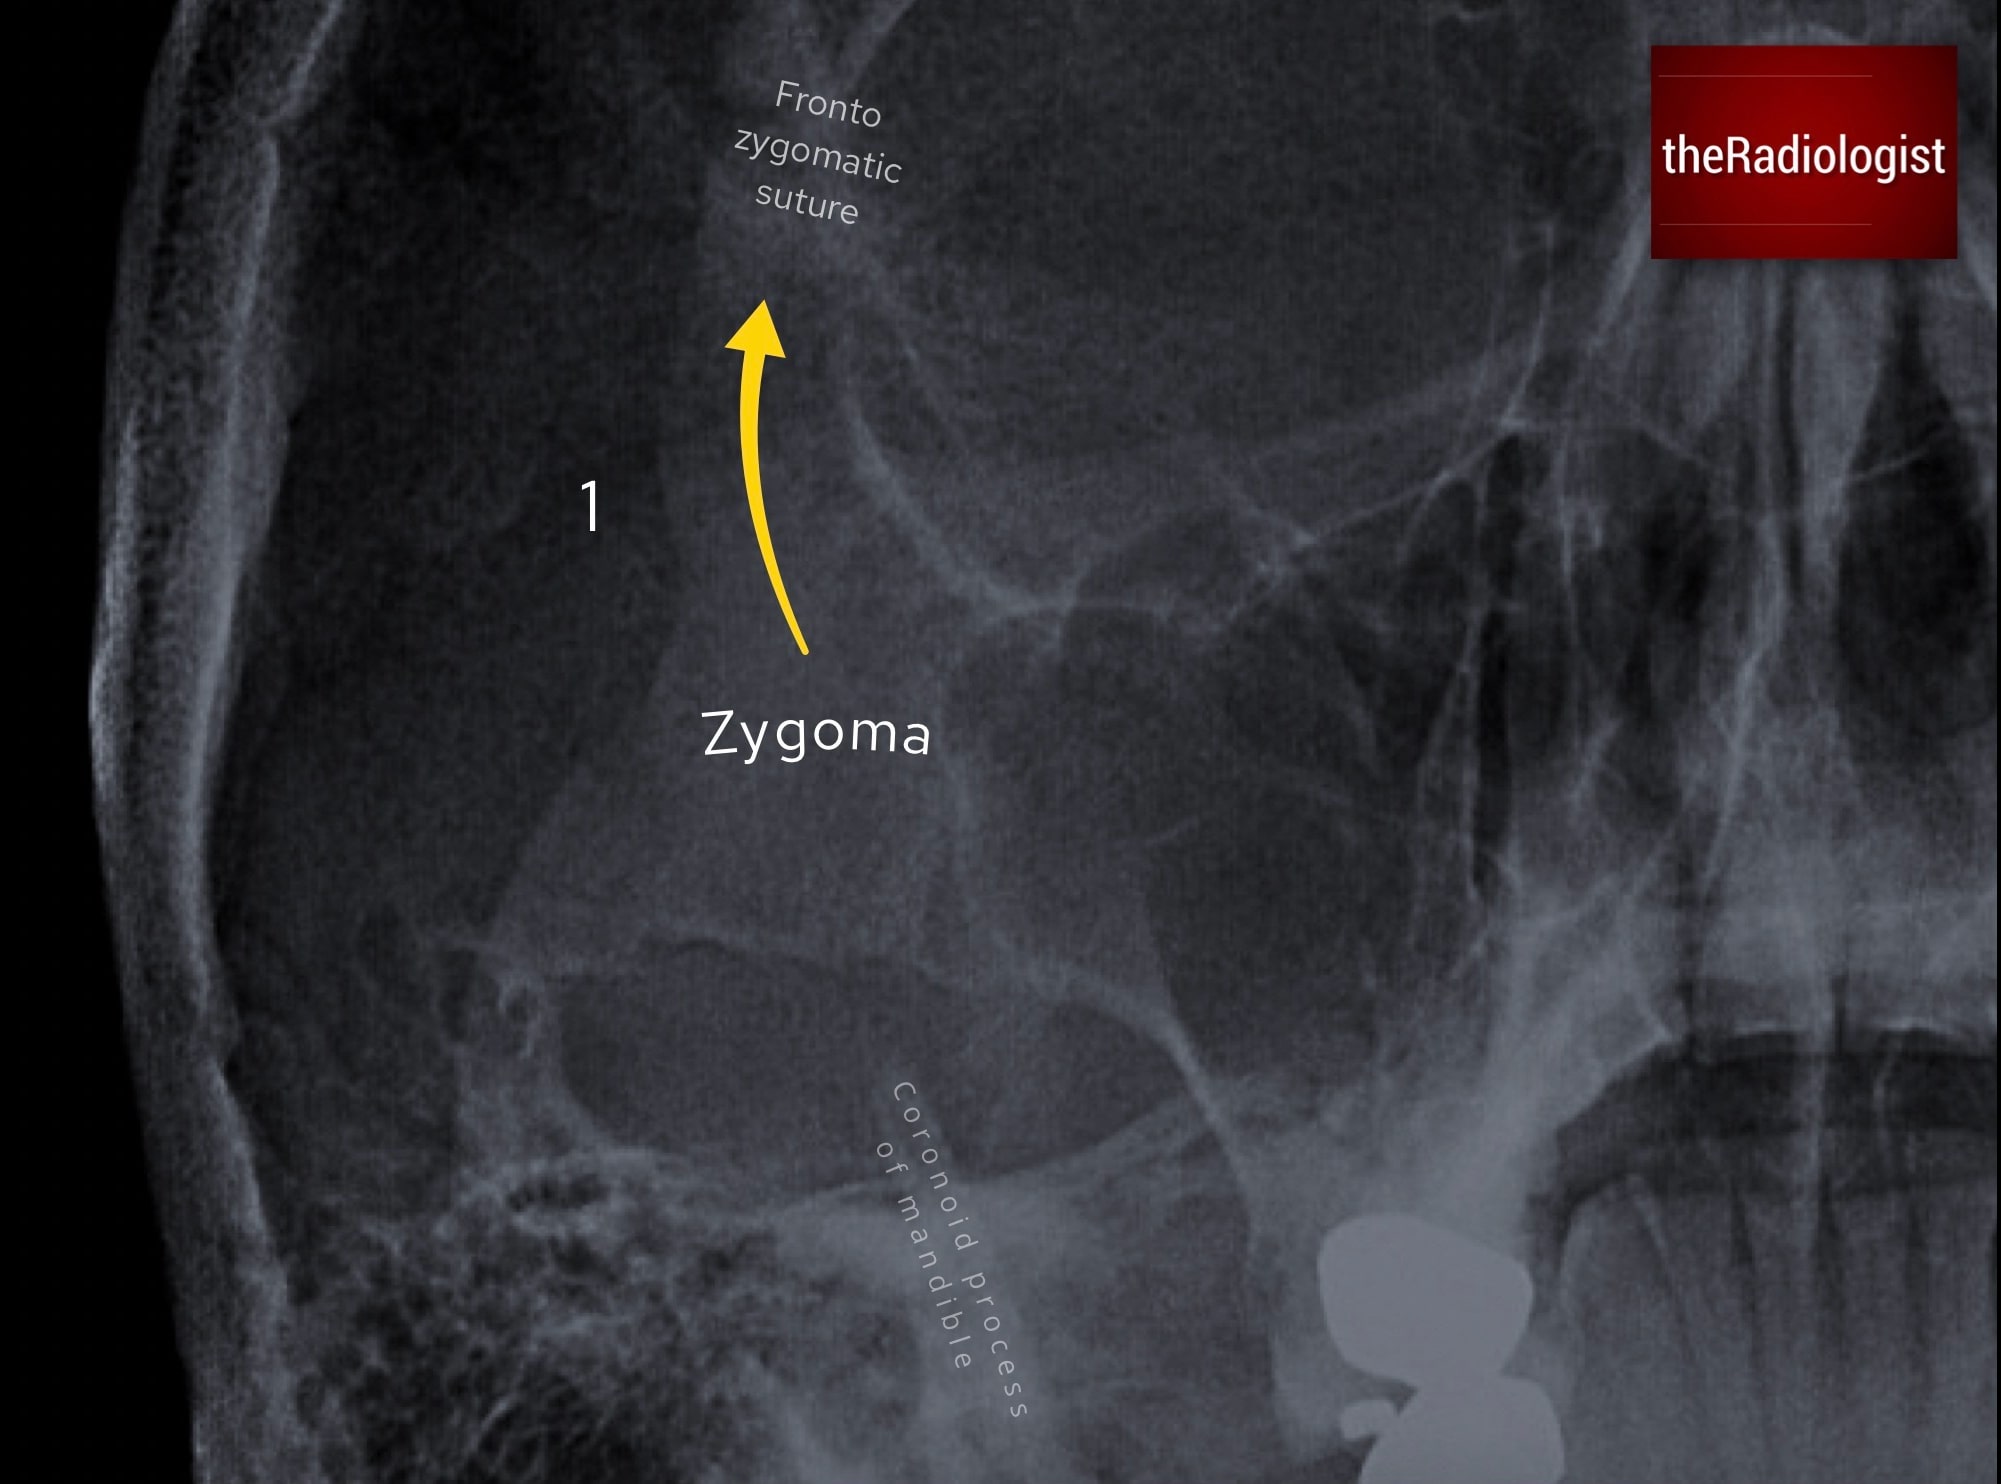

1. Look for a zygomaticomaxillary complex fracture

Begin by finding the zygoma, the keystone of the cheek, and then fan outwards in several directions. At each margin, carefully trace the cortex from end to end, looking for any break or step in the cortex that could represent a fracture. Comparing with the contralateral side can help prevent you being misled by normal variation or overlapping structures.

Find the zygoma and fan out in four directions looking for a fracture.

Fronto-zygomatic suture

First, go superiorly and assess the frontal process of the zygoma and its articulation with the frontal bone. A subtle widening or step at the fronto-zygomatic suture may be the only clue to a fracture at this site.

Go superiorly and assess the frontal process of the zygoma and compare the fronto-zygomatic suture with the other side to see if it is widened.